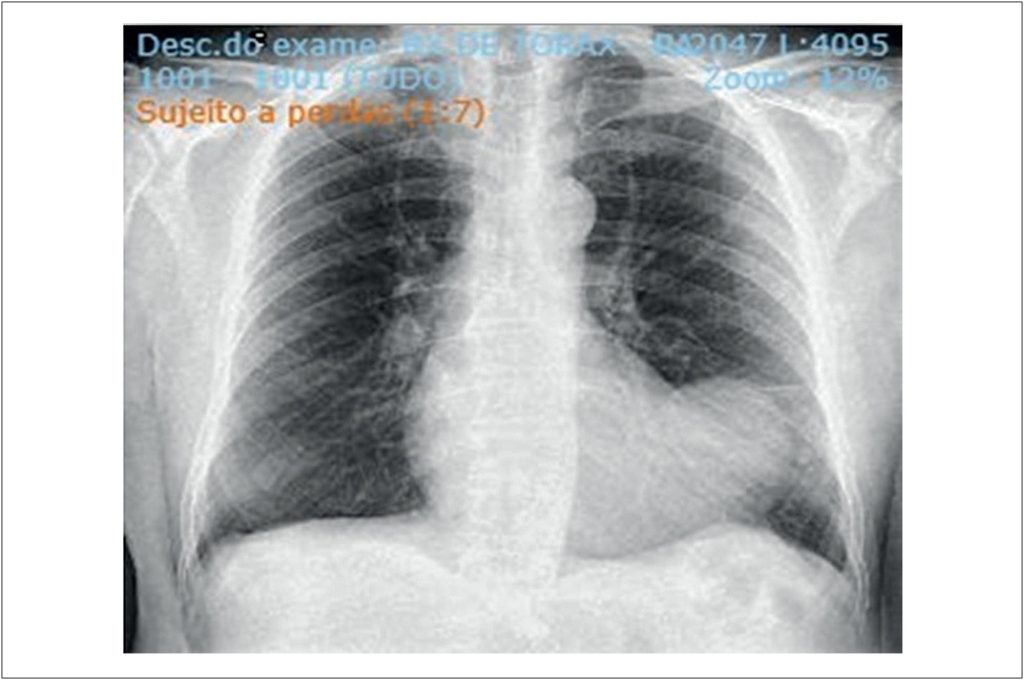

Left ventricular (LV) pseudoaneurysm is a rare complication of acute myocardial infarction (AMI). We report the case of a 67-year-old male patient seen in 2024. Following an AMI in 2019, the patient was diagnosed with a LV pseudoaneurysm after complaining of dyspnea and undergoing imaging tests including echocardiogram and magnetic resonance imaging. The patient underwent aneurysmectomy and revascularization surgery, progressing satisfactorily during the postoperative period.